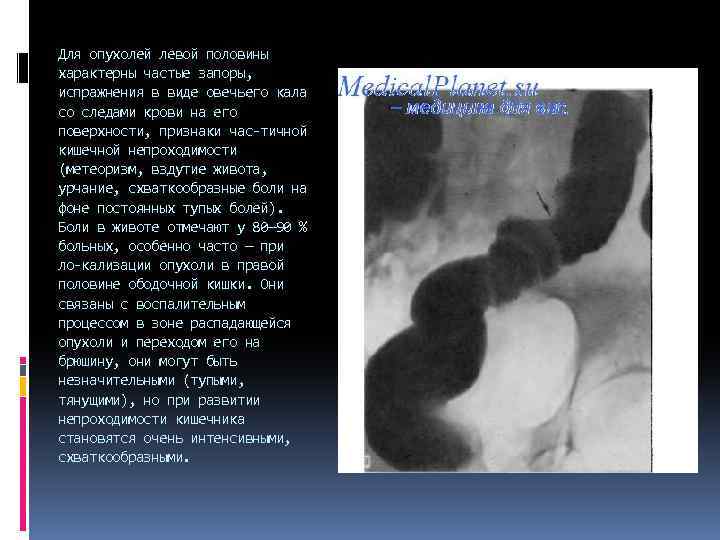

Для опухолей левой половины характерны частые запоры, испражнения в виде овечьего кала со следами крови на его поверхности, признаки час тичной кишечной непроходимости (метеоризм, вздутие живота, урчание, схваткообразные боли на фоне постоянных тупых болей). Боли в животе отмечают у 80— 90 % больных, особенно часто — при ло кализации опухоли в правой половине ободочной кишки. Они связаны с воспалительным процессом в зоне распадающейся опухоли и переходом его на брюшину, они могут быть незначительными (тупыми, тянущими), но при развитии непроходимости кишечника становятся очень интенсивными, схваткообразными.